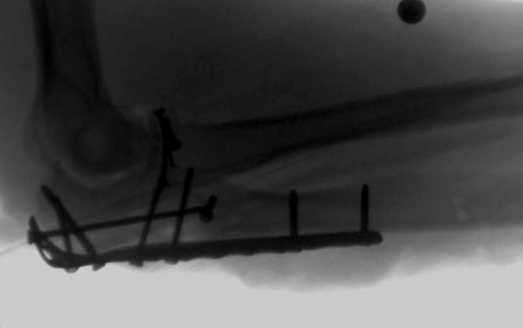

1 вариант применен ACUMED локинг пластина

2 вариант